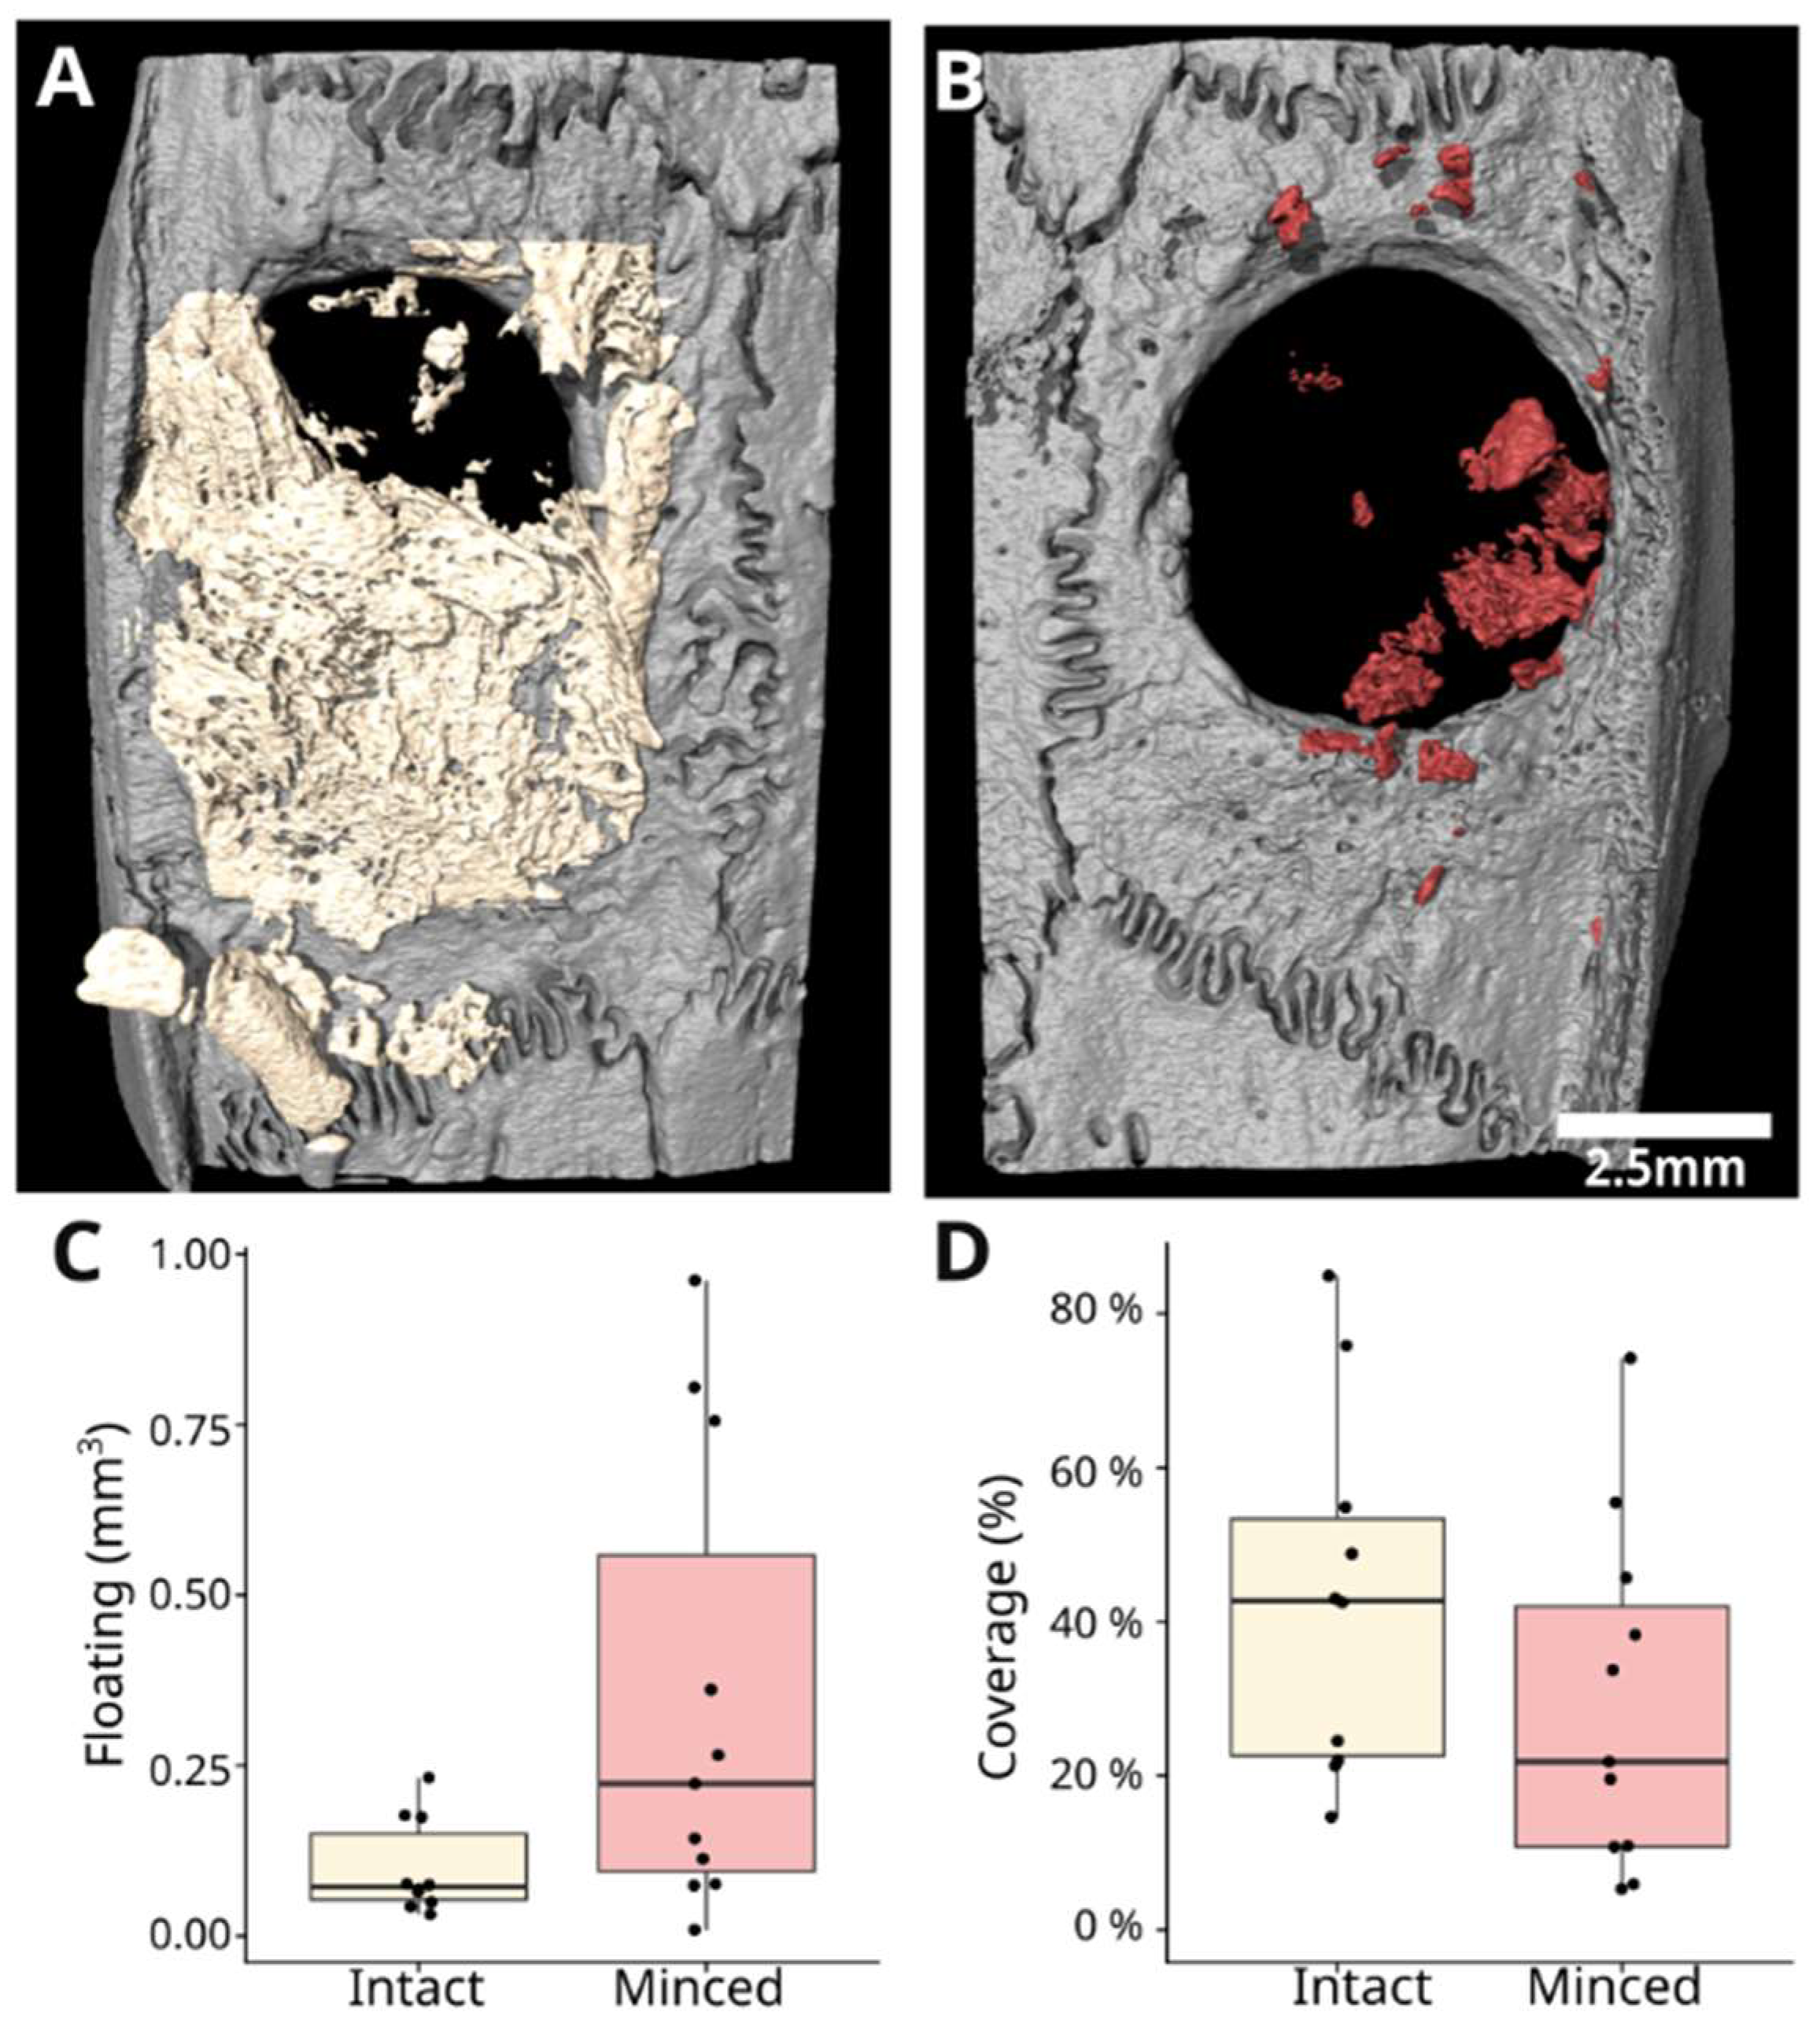

3.2. Intact Collagen Membranes: Histological Analysis

3.3. Minced Collagen Membranes: Histological Analysis